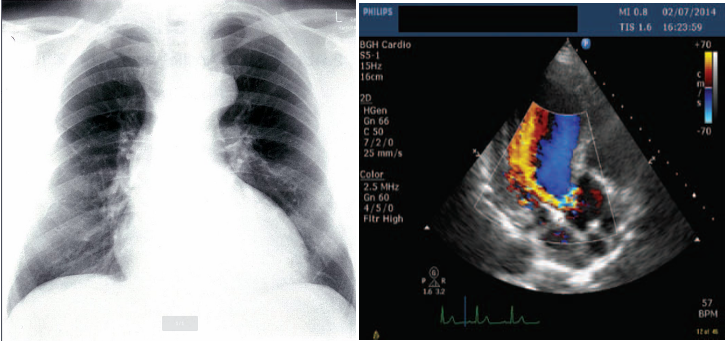

Investigations

- Echocardiography and Doppler (TTE): First-line diagnostic tool: assess the severity: LV dilatation.

- CXR:

- Cardiomegaly: Dilating ascending aorta.

- Pulmonary edema (Acute AR) with normal cardiac size.; crepitation

Imaging

A. Echocardiogram:

- Allows visualization of the origin of the regurgitant jet and its width, detection of aortic valve pathology and ventricular hypertrophy.

B. CXR:

- May demonstrate cardiomegaly.

- Dilated ascending aorta.

- Calcification may be seen.

A 30-year-old woman presented with shortness of breath on exertion and occasional chest pain. Does not use tobacco, alcohol, or illicit drugs. She immigrated from Peru two years ago with her family. Her temperature is 36.4°C; pulse is 115/min, respirations are 24/min, and blood pressure is 130/60 mm Hg. Physical examination shows pulsations of the nail bed. Cardiac examination shows an abnormal heart sound over the left sternal border on auscultation (see image below). Which of the following maneuvers will likely decrease the intensity of this heart sound?